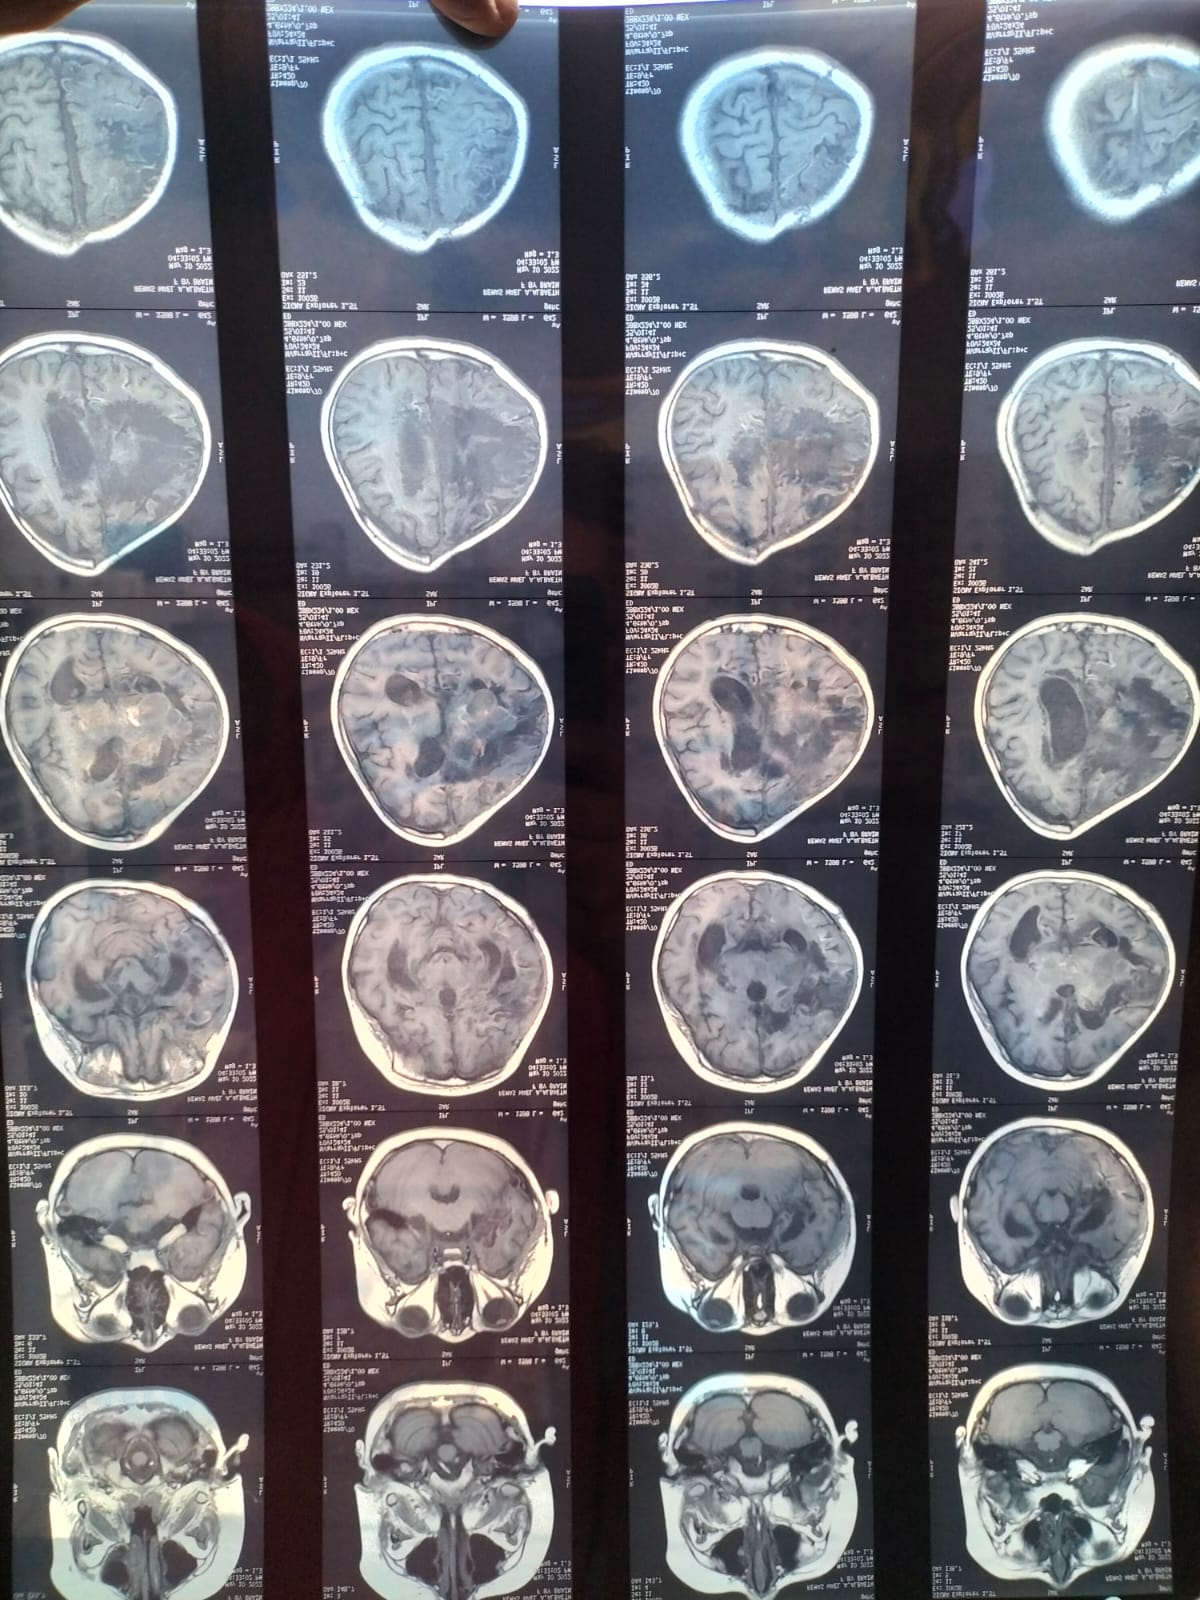

وقالت والدة الطفلة ريماس وائل التي تعيش في محافظة الإسكندرية لـ القاهرة 24، إن الطفلة تعاني من سرطان جذع الدماغ منذ عام ونصف، والذي حدث فجأة لها، حيث إنها لم تكن تعاني من أمراض سابقة، لتصاب برعشة في الجسم وظهور هزات في القدمين وعدم توازن، وبعد إجراء الفحوصات الطبية والإشاعات في مستشفى الإسكندرية العام، أفصح الطبيب أن الطفلة تعاني من ورم في جذع المخ.

وأوضحت والدة الطفلة، أنه تم أرسالها لمستشفى 57357، ولكن المستشفى رفض الطفلة، نظرا لتأخر حالتها، موضحين ذلك أن الطفلة في حالة متأخرة، ولم يقدموا الرعاية الطبية لها، مشيرة إلى أنهم أعطوا الطفلة حبوب كيماوي، حيث أدخلت الطفلة في غيبوبة مستمرة 6 أشهر حتى الآن، وظهر ذلك في منع البلع والكلام والأكل عن طريق الأنف.

وأكدت والدة ريماس، أنه بعد الفحوصات في مستشفيات عديدة، أجرت عملية في مستشفى 57357 نتج عنها تأثيرات سلبية على الطفلة، أبرزها أن الحالة ساءت أحوالها، وتم إزالة نصف عظام المخ وذلك حسبما أوضح المستشفى لكي يتمدد الورم، وبعد ذلك الطفلة خرجت من المستشفى إجباري وذلك لصعوبة حالتها.